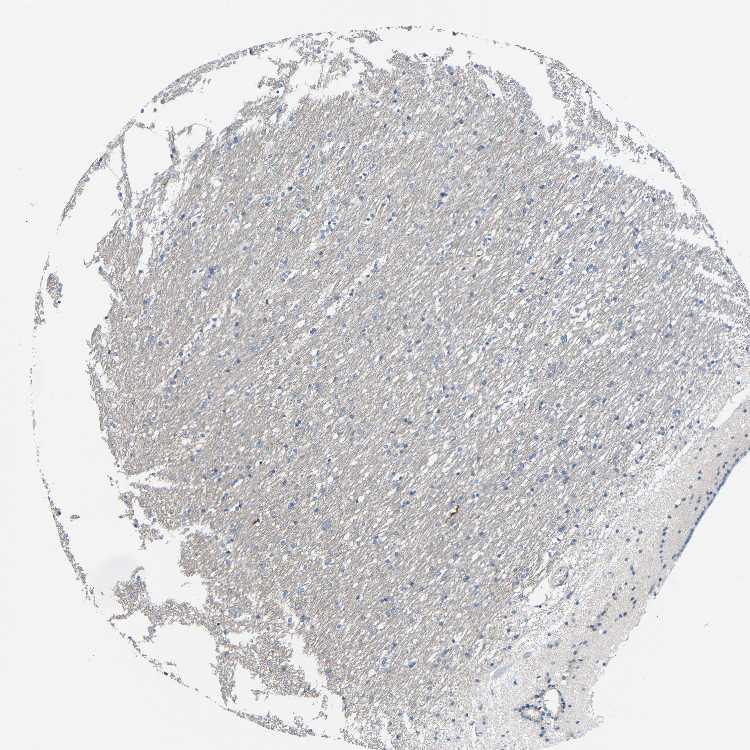

CAUDATE - Antibody stainingi

Antibody staining in the annotated cell types in the current human tissue is reported as not detected, low, medium, or high, based on conventional immunohistochemistry profiling in selected tissues. This score is based on the combination of the staining intensity and fraction of stained cells.

Each image is clickable and will lead to virtual microscopy that enables deeper exploration of all samples and also displays staining intensity scores, fraction scores and subcellular localization as well as patient and tissue information for each sample.

Antibody HPA011894

Glial cells Not detected

Neuronal cells Low